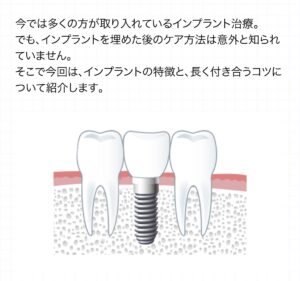

こんにちは!

池田歯科大濠クリニックではインプラント治療をするだけではなく、

インプラント治療後のケアの方法をみなさまにお伝えしておりますが、

上手く出来ているか気になる方はご遠慮なく、メンテナンス時にご質問ください。

過去に池田歯…